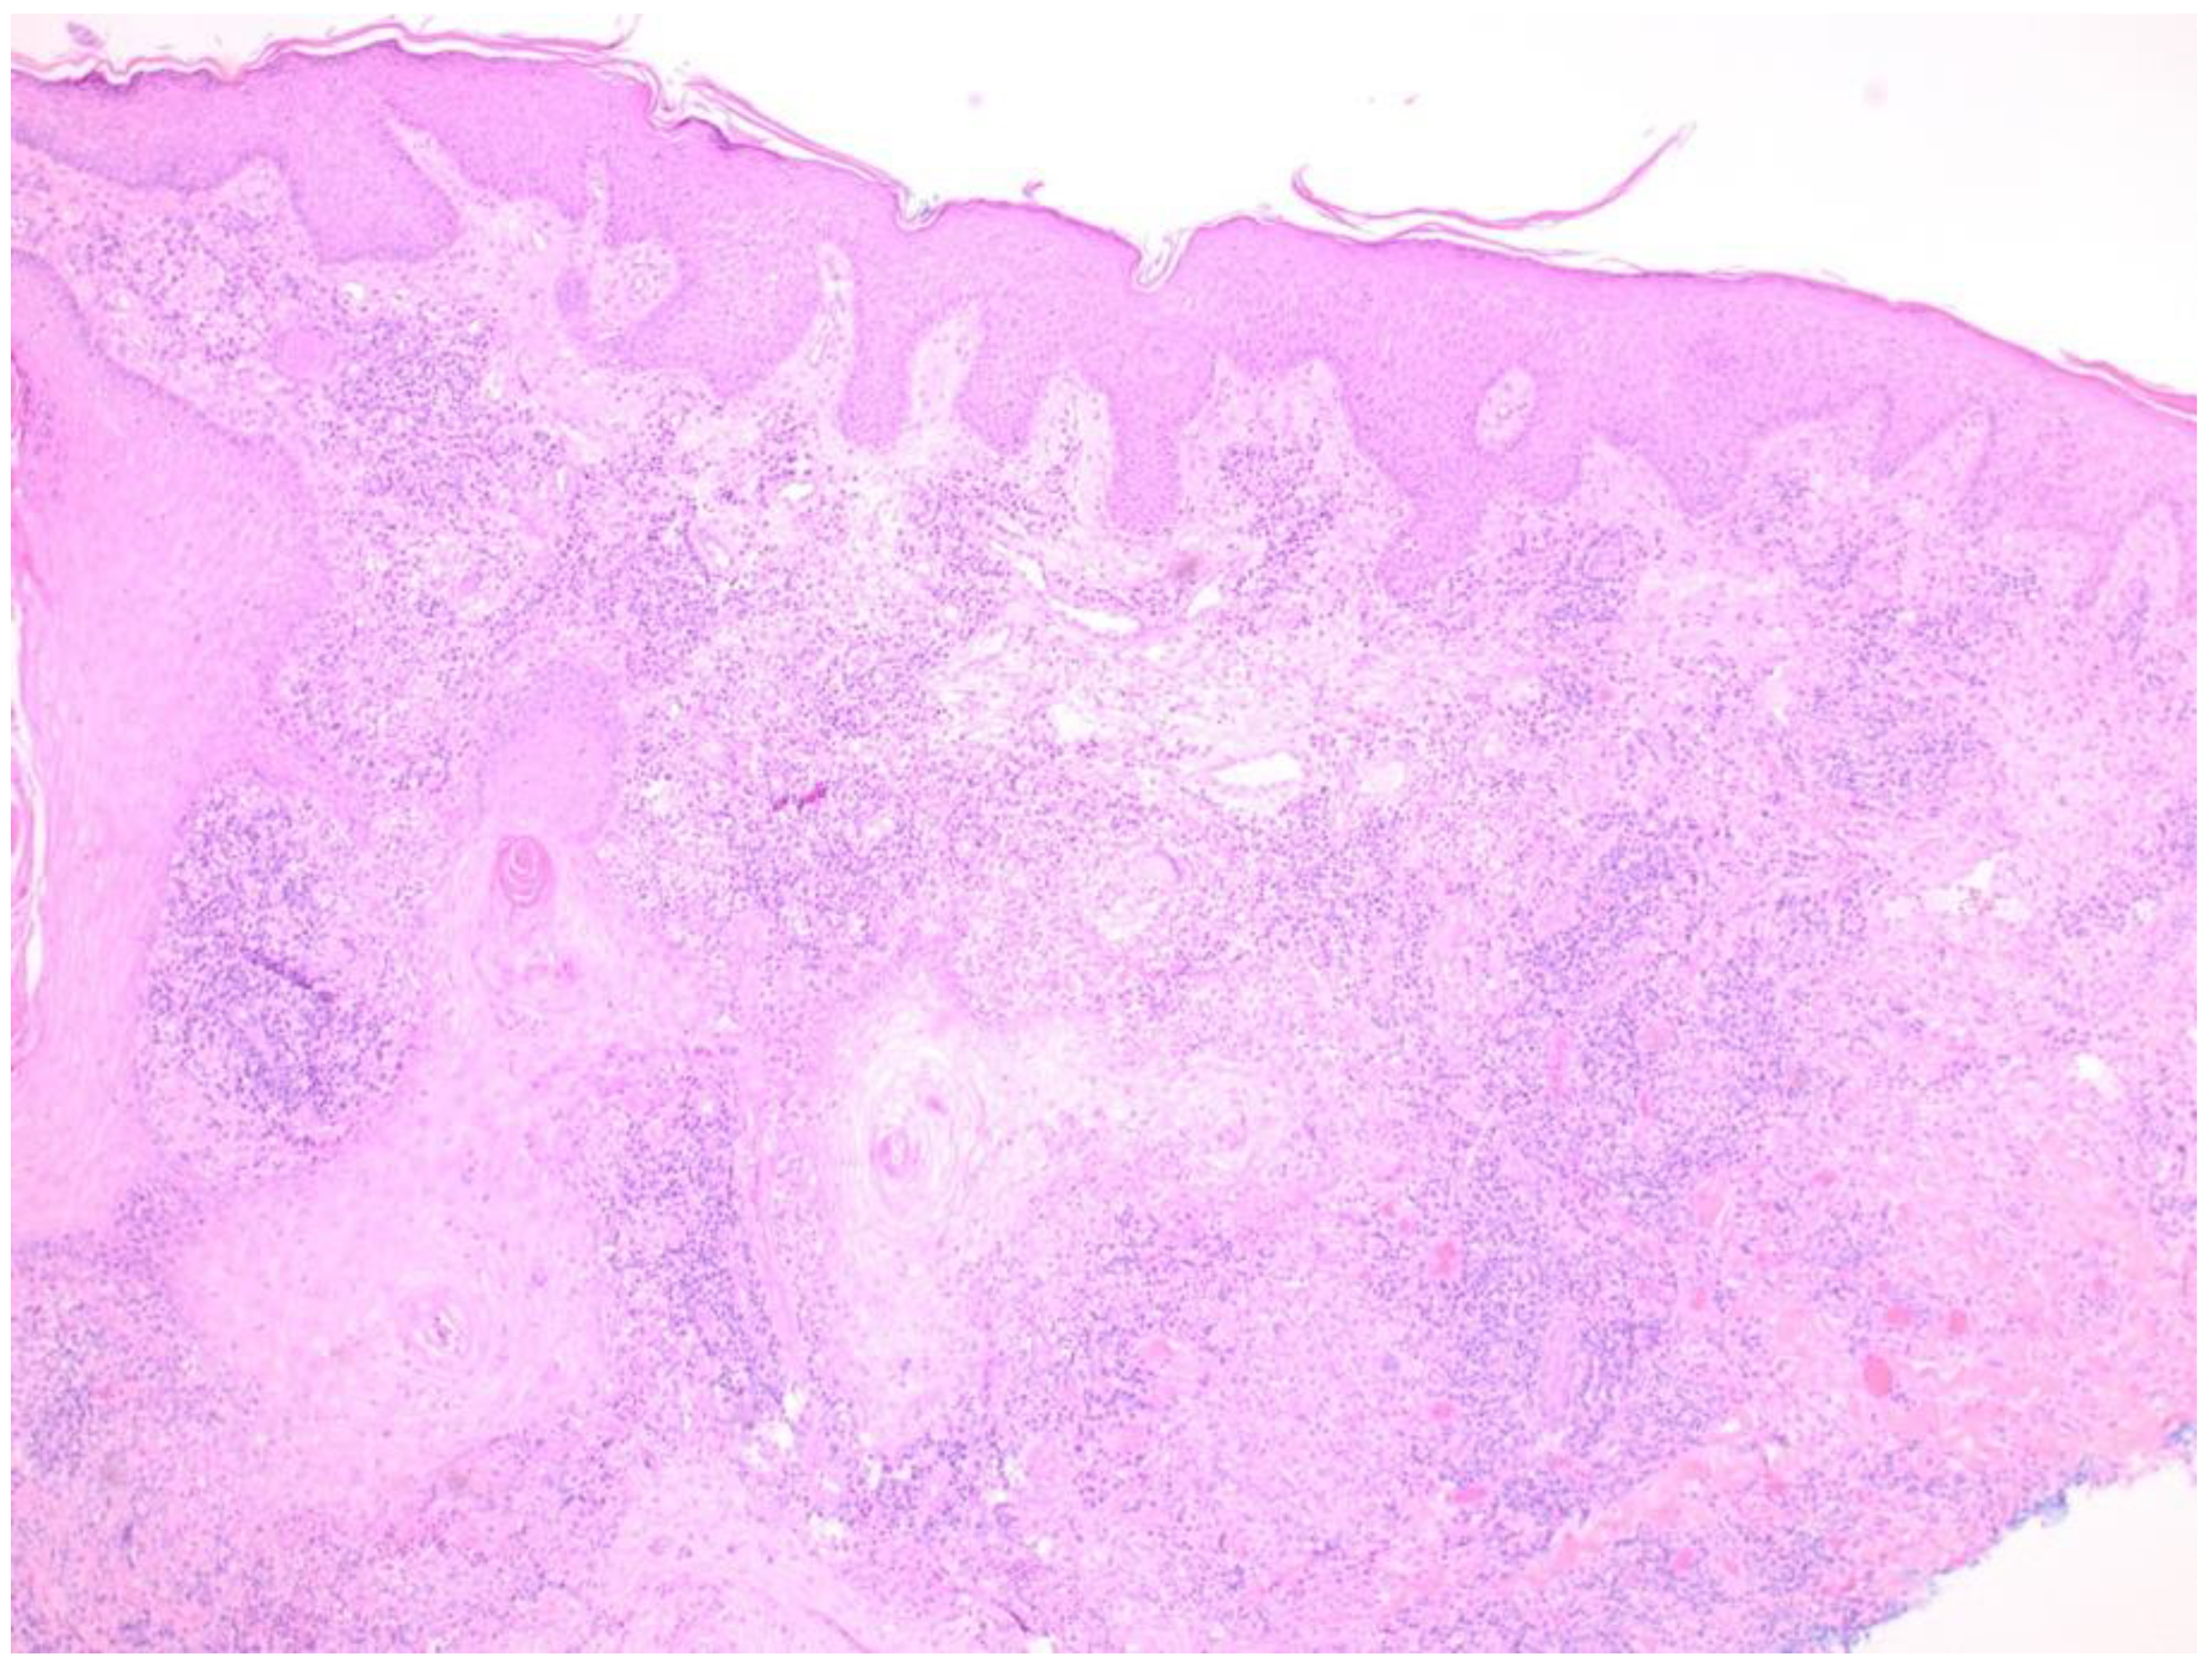

3.5. Skin Manifestations of Coccidioidomycosis and in This Patient